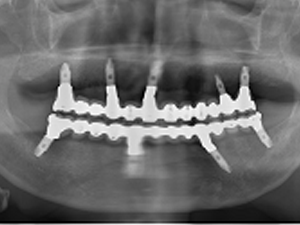

Same day implant is our implant treatment program for people who have been unable to eat with full dentures or who have given up on implants because they do not have enough bones.

The strongest advantage of this method is that there are less physical burden since the surgery will finish in a shorter period of time than a conventional operation. This is because the minimum number of implants to be inserted is 4 for patients who do not have any teeth, which is very small.

Since placing implants and provisional teeth are done on the same day, patients can eat food on the day of the surgery with teeth.